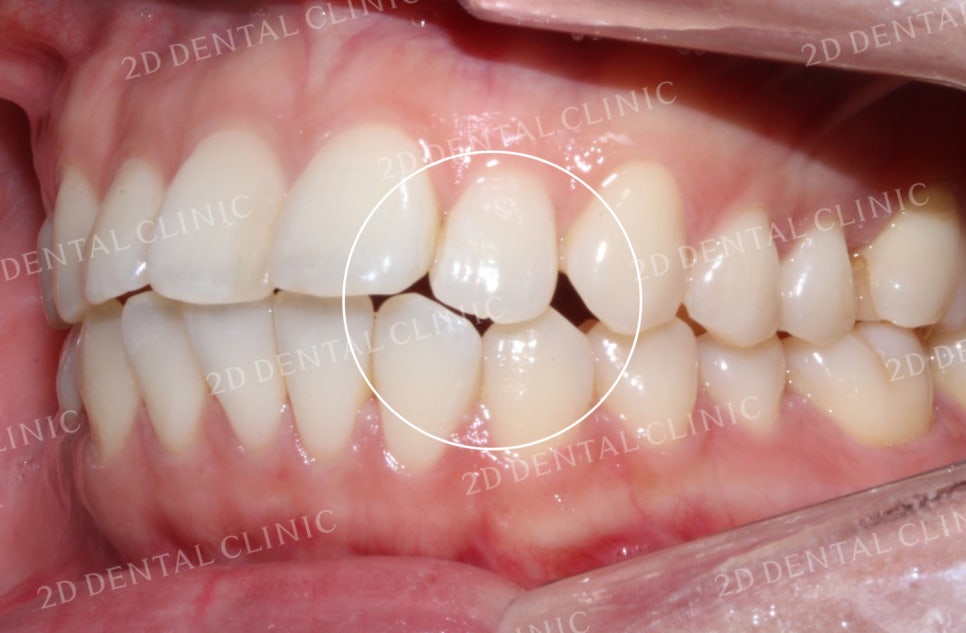

좌우의 안모 사진입니다.

표시된 부분에서 완전히 맞물리지 못한

치아 사이의 틈이 발견되고 있네요.

이러한 교합면 사이의 빈 공간은

음식물 섭취 시 불편을 유발하는 원인 중 하나입니다.